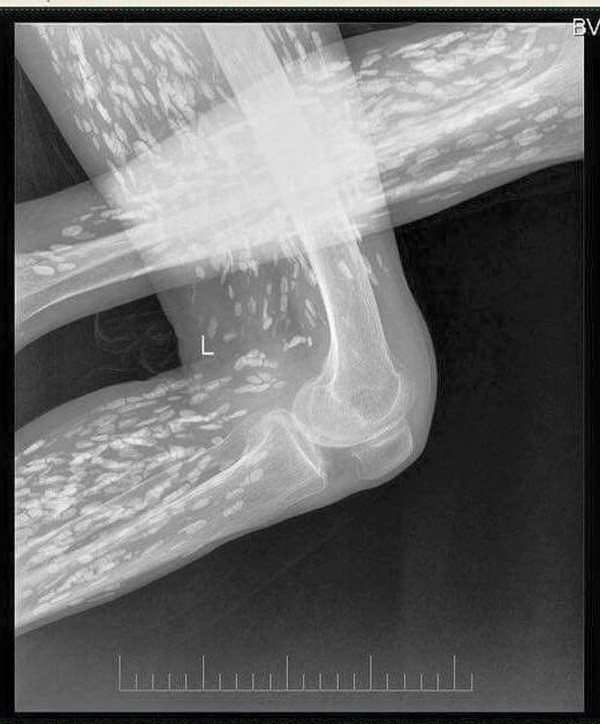

Vào tháng 3 năm ngoái, các bác sĩ tại Bệnh viện Trường Đại học Y Quý Châu đã vô cùng bất ngờ khi phát hiện 30 quả trứng sán dây "nở" bên trong não một người đàn ông trung niên họ Wu nhập viện do đau đầu và buồn nôn trong suốt nửa năm. Họ tin rằng sán dây lợn đã xâm nhập vào não ông ta bởi ông đã ăn thịt lợn nhiễm sán hoặc chưa chín.

Số trứng sán mà bác sĩ lấy ra từ bên trong não của ông Wu.

Ông Wu kể với các bác sĩ rằng bản thân ông từng ăn thịt sống, sau đó ông thấy xuất hiện các triệu chứng đau đầu, nôn mửa và co giật. Chụp cộng hưởng từ (MRI) não ông Wu cho kết quả có hàng chục trứng sán dây, chúng đã khiến ông này bị não úng thủy. Đội ngũ bác sĩ tại bệnh viện đã tiến hành phẫu thuật mở sọ cho ông Wu và loại bỏ số trứng cùng sán dây khỏi não của bệnh nhân 46 tuổi này.

Bác sĩ phải tiến hành phẫu thuật mở sọ cho ông Wu và loại bỏ số trứng cùng sán dây.

Những con ấu trùng vẫn còn động đậy bên trong quả trứng, vì vậy, khi phẫu thuật các bác sĩ đã vô cùng cẩn trọng để không khiến trứng vỡ. Sau cuộc phẫu thuật, ông Wu còn trải qua nhiều cuộc điều trị khác để loại bỏ hoàn toàn sán dây bởi nếu vẫn còn sót lại, chúng có thể gây tổn thương mô não của ông.